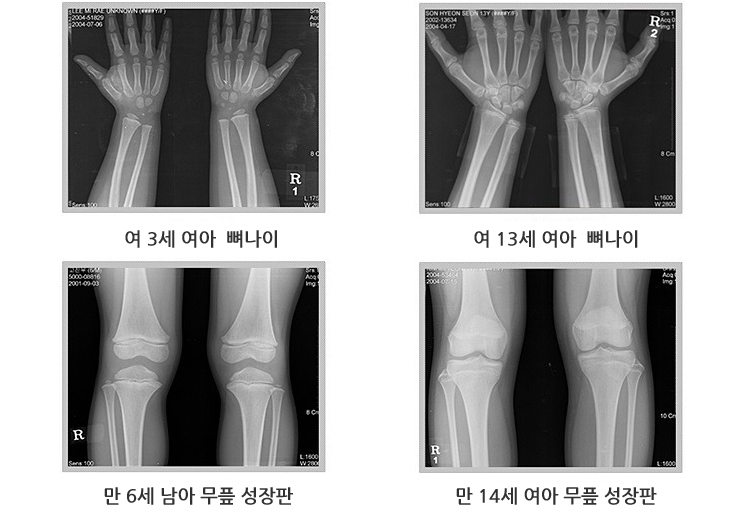

이를 위해서는 최소한 6~12개월 이상 추적관찰 하는 것이 좋습니다. 학교 건강기록부에 기록되어 있는 키와 체중은 성장 속도를 평가하는데 좋은 자료가 됩니다.■ 골연령 측정

왼쪽 손목의 방사선 사진을 찍어 측정하며, 정상 표준과 대조해서 골연령을 판정합니다.

골연령 지연 여부에 따라 저신장의 원인을 감별할 수 있고, 성장판이 닫힌 경우라면 더 이상 성장은 일어날 수 없습니다.